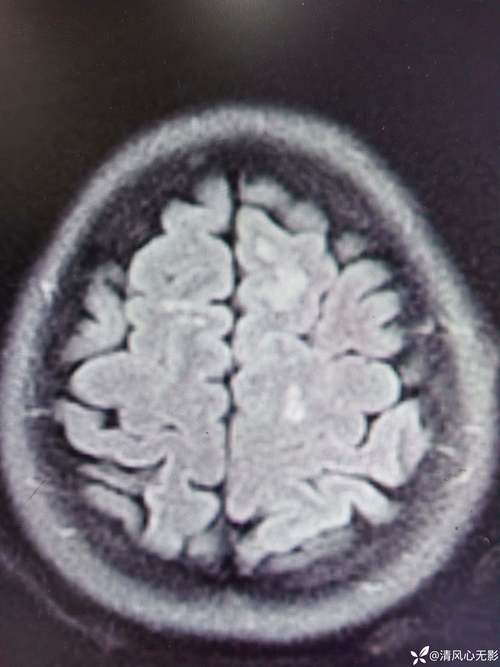

- “缺血灶”:指由于缺血导致脑组织已经发生轻微、不可逆的损伤后留下的“疤痕”或“印记”,在影像学(如CT或MRI)上,它通常表现为一个小点状的信号异常区域。

脑内多发缺血灶就像是大脑里出现了多个小小的“陈旧性伤口”或“小疤痕”。 这些损伤通常是陈旧的,意味着它们发生在过去,而不是正在发生的急性事件。

(图片来源网络,侵删)